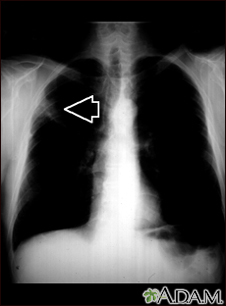

Lung mass, right upper lung - chest x-rayBackLung mass, right upper lung - chest x-rayThis picture is a chest x-ray of a person with a lung mass. This is a front view, where the lungs are the two dark areas and the heart and other structures are visible in the middle of the chest. The x-ray shows a mass in the right upper lung, indicated with the arrow (seen on the left side of the picture). E-mail FormEmail ResultsName:Email address:Recipients Name:Recipients address:Message: